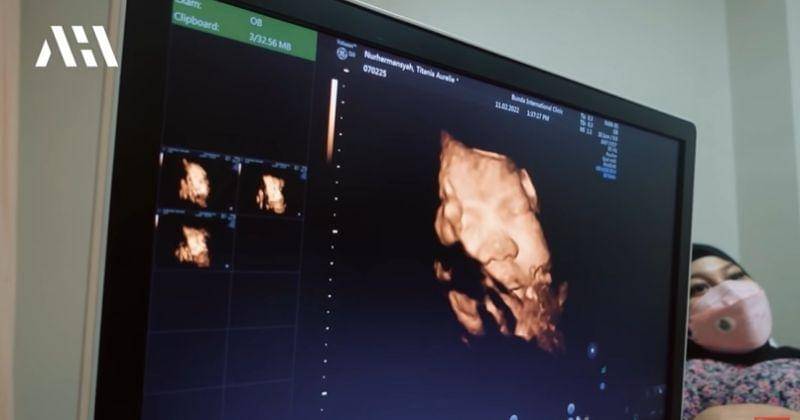

3. Mengecek kandungan ke dokter, wajah Baby A persis Atta Halilintar

Sebagai persiapan kelahiran anak pertamanya, Aurel dan Atta juga rutin cek kandungan. Saat melakukan USG, pasangan ini melihat wajah sang Anak.

Rupanya wajah Baby A yang berjenis kelamin perempuan itu sangat mirip dengan Atta Halilintar. Aurel juga sudah mulai merasakan gejala-gejala jelang persalinan.

Saat cek kandungan terakhir, Aurel Hermansyah begitu senang karena berat anaknya sudah 3 kg. Baby A dalam kandungan juga sangat sehat.

"Wah mukanya aku banget," tutur Atta sembari melihat hasil USG Aurel.